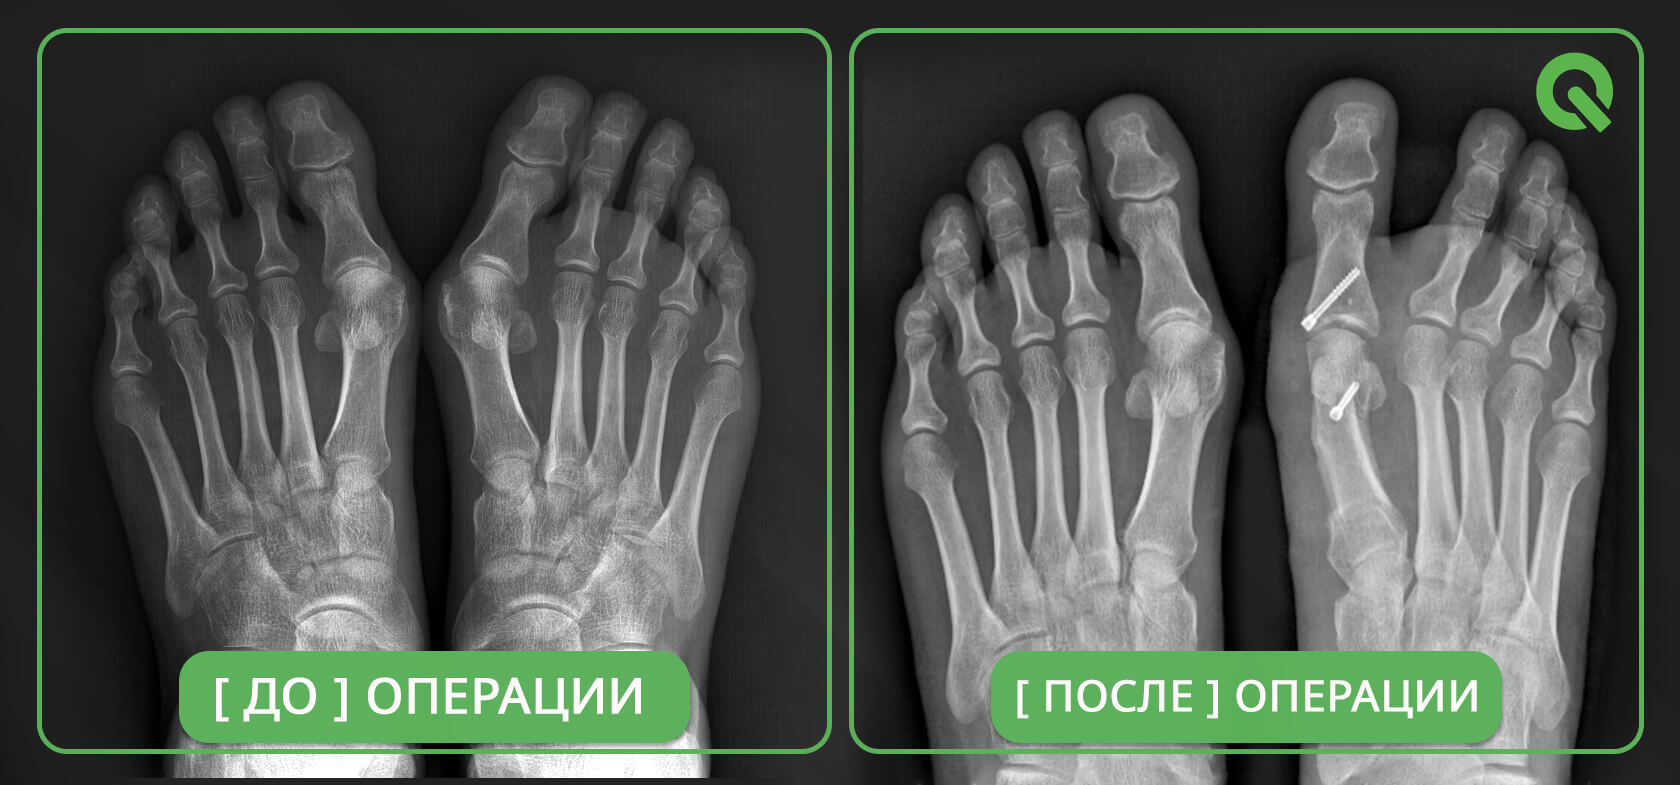

Операция Вальгусная Деформация Фото

Операция Вальгусная Деформация Фото 113 фотографий